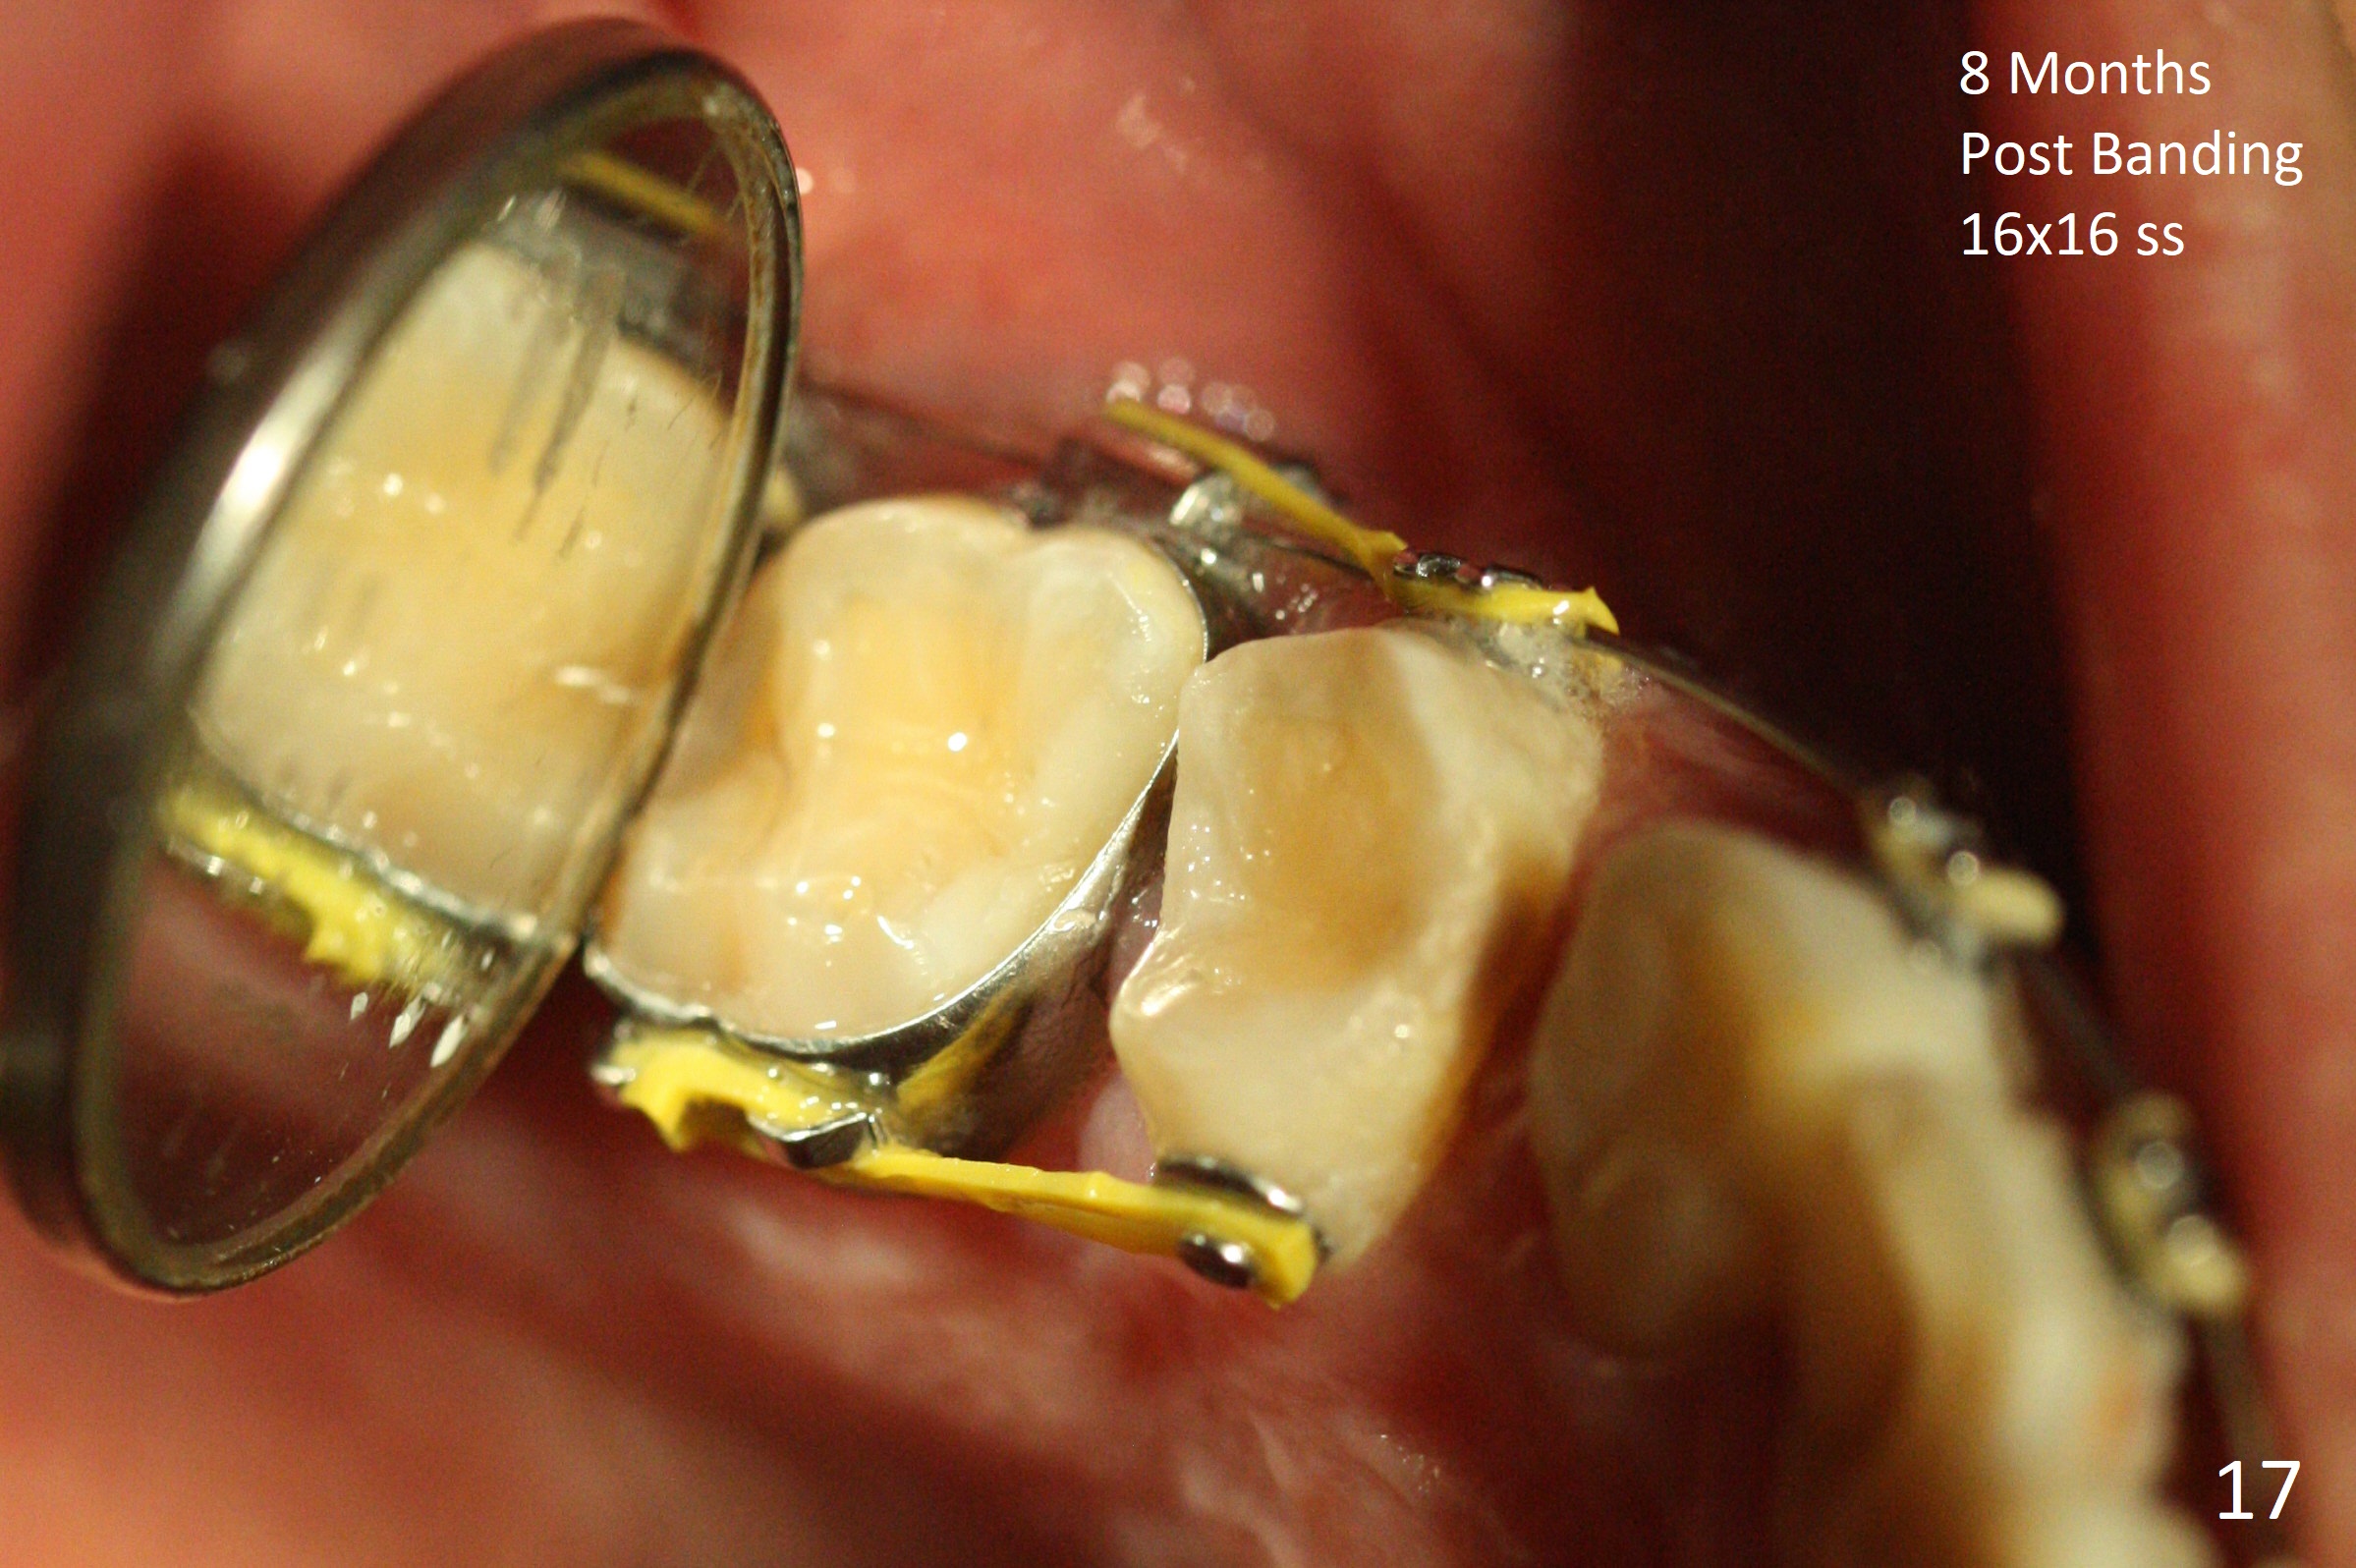

Severe crowding (Fig.1-7) appears to be alleviated especially 2 months after UR5 extraction. Diastemata seem to form mesial and distal to UR2 (Fig.8). Because of severe wear at UR3 (Fig.6), there is no bracket placement differential around it (Fig.8 (14 niti wire)). Lower bands and brackets are placed a week later (Fig.9-11). Because of tight space between LR4 and the opposing tooth (Fig.10), band adhesive is applied to L7 occlusal surface to open the bite (Fig.9). There is an abrupt kink of 12 niti wire between LL4 and 6 (Fig.11). The latter does not improve much in a month; the wires remain the same (Fig.12). For LL2, LR4 has been retracted for ~ 1 month (Fig.13). There is mild tension when 18 ss wire is inserted between LL4 and 6 five point five months post banding (Fig.14). UR4 has been distalized for a month using buccal power chains x3 resulting in rotation; to counter the rotation, a lingual button is placed with power chain x3 lingual and x2 buccal (Fig.15). With space gaining, it is time to finish definitive filling (Fig.16 *). Next visit check midlines, overjet, interdigitation, and molar classification. R4s distalize, but associate with rotation because of power chains buccal and lingual 8 months post banding (Fig.17,18). With the use of the same wires, power chains are applied lingual to continue distalization and rotation correction (Fig.20,21). Lingual buttons are placed at L2s buccalization (Fig.19) and mesialization (Fig.22,23). It appears that space should be created distal to LR3. That is that the lower anterior teeth should be shifted to the right, although it may be not appropriate for the midline.